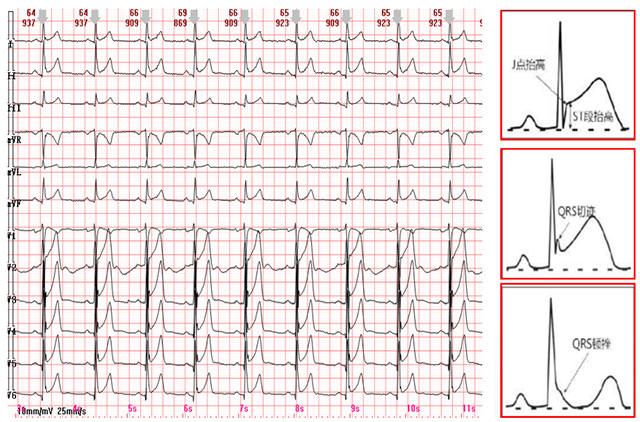

“醫(yī)生,我心電圖上描述的‘J波伴ST段抬高’是啥意思?是不是有心臟病???”心腦電圖科總能接到不少這樣的咨詢。28歲的程序員小周就是其中之一,他看到報告上“異常”字樣,連夜查了好多資料,越看越擔心。其實,他這種情況大概率是“早期復極”——一種...